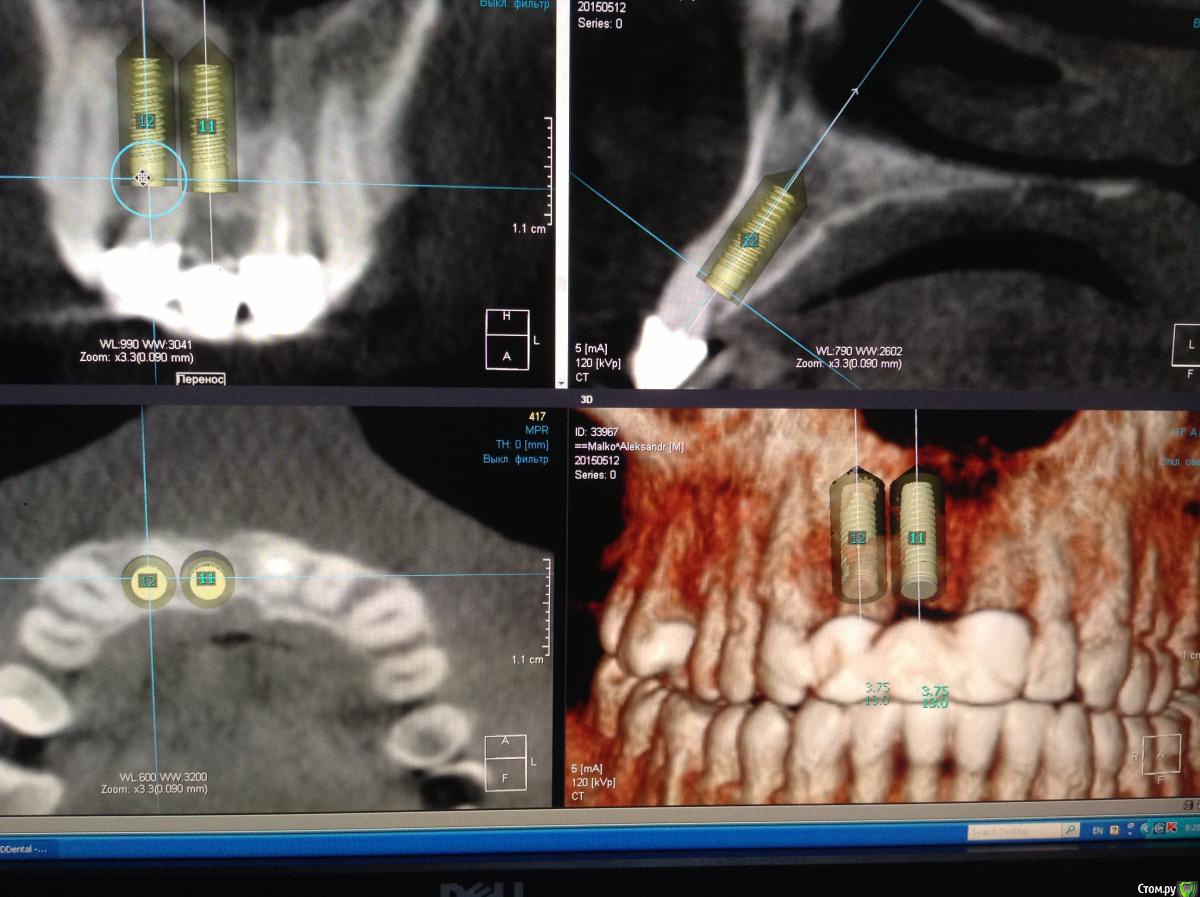

Pro100Andre Опубликовано 10 июля, 2015 Автор Поделиться Опубликовано 10 июля, 2015 Вот так получилось 12 терапевты не решились перелечивать Ссылка на комментарий

zzkz Опубликовано 10 июля, 2015 Поделиться Опубликовано 10 июля, 2015 фото во рту покажите?мне кажется близко др к др. и может пострадать сосочек. А может срез такой Ссылка на комментарий

JIM Опубликовано 12 июля, 2015 Поделиться Опубликовано 12 июля, 2015 Какой тут может быть сосочек??? Рецессии бы не было!Удачи оператору и пациенту Ссылка на комментарий